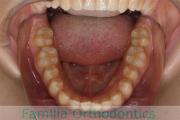

No.23V-061

- 主な症状:

- 叢生

- その他の症状:

- 上下顎前突

- 年齢:

- 23歳

- 性別:

- 女性

- 抜歯部位

- 上:

- 44

- 下:

- 主な使用装置:

- FEA 022

- 治療にかかった費用:

- 88万円

でこぼこを綺麗に並べたいということで来院されました。上下左右から小臼歯を抜歯して、マルチブラケット法を2年半、30回程度通院していただいて行いました。

かなり強い叢生(でこぼこ、凹凸、ガタガタ)のため、保定をしっかりしないと後戻りのリスクが高いケースといえます。

- ≫治療前

-

上顎

下顎

前歯の関係など

右側

正面

左側